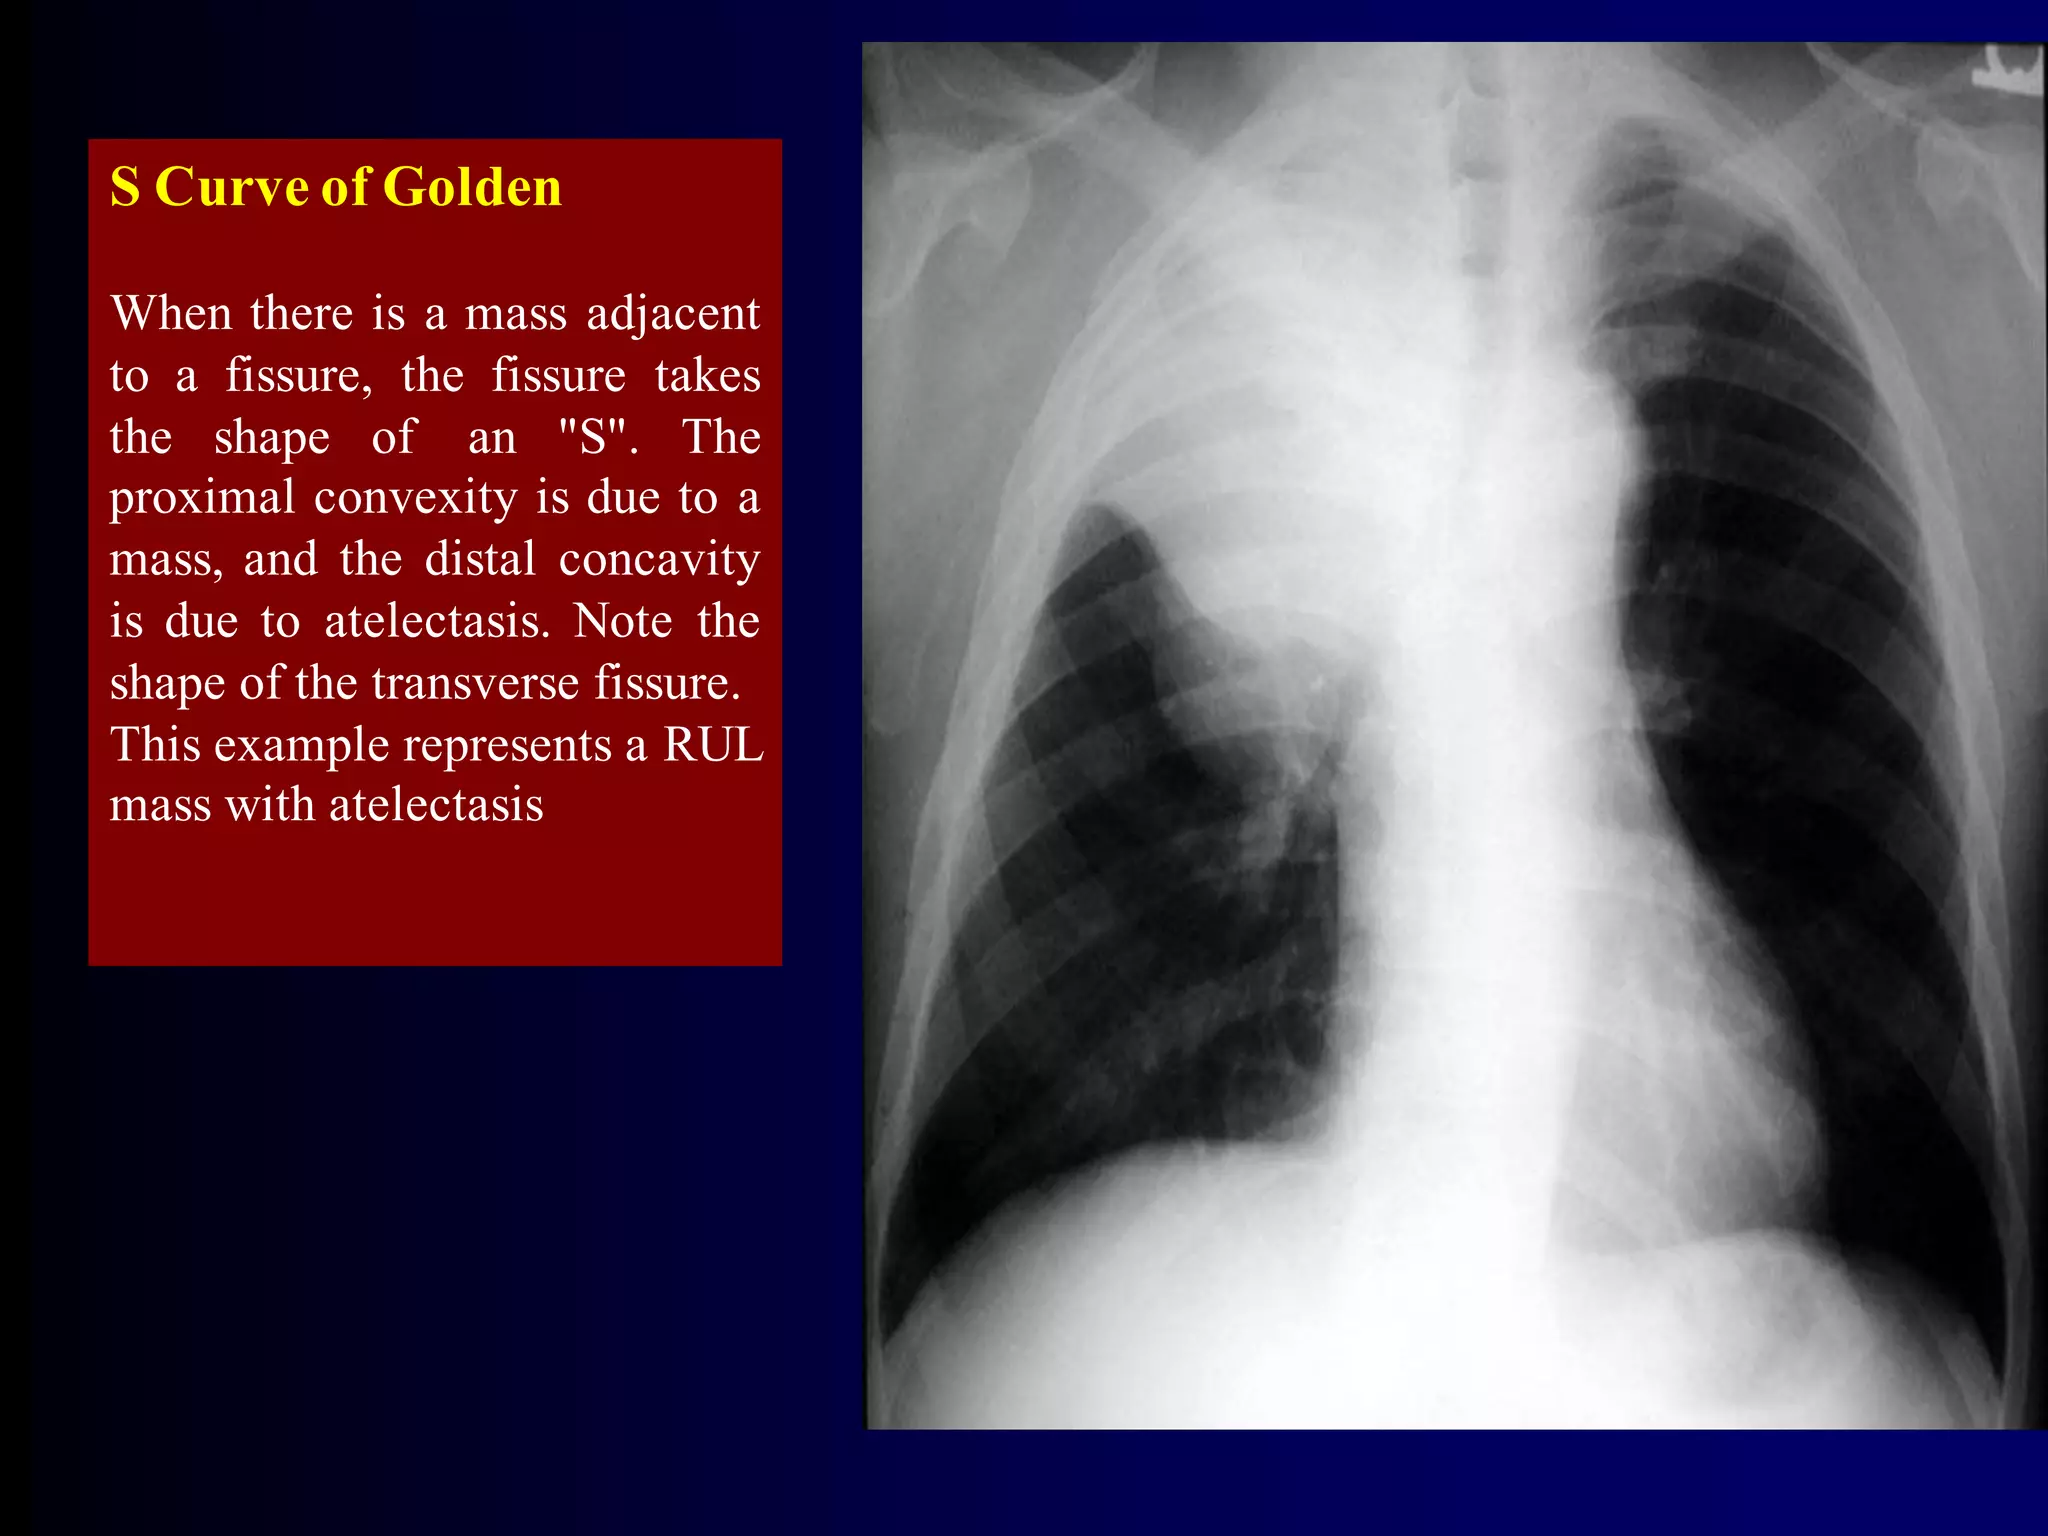

S Curve of Golden

When there is a mass adjacent

to a fissure, the fissure takes

the shape of an "S". The

proximal convexity is due to a

mass, and the distal concavity

is due to atelectasis. Note the

shape of the transverse fissure.

This example represents a RUL

mass with atelectasis